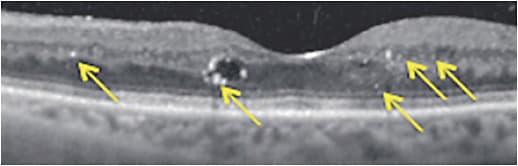

Dr. Sadda: Studies have linked disorganization of the retinal inner layers (DRIL) on OCT of eyes with DME to poorer visual acuity10 and less improvement in vision if it persists after resolution of the macular edema (Figure 3).11 In terms of the outer retinal bands, 2 areas also thought to have an impact on visual prognosis are the ellipsoid zone, which was formerly referred to as the photoreceptor inner segment/outer segment (IS/OS) junction, and the external limiting membrane (ELM).12,13

If the ellipsoid zone appears to be damaged but the ELM is intact, there may be an opportunity for vision recovery.13 We see that dynamic in other diseases as well, such as central serous chorioretinopathy (CSCR). However, when the ELM is also disrupted, it’s often a sign of irreversible damage with a poor visual prognosis, perhaps because it signifies irreversible Müller cell damage.